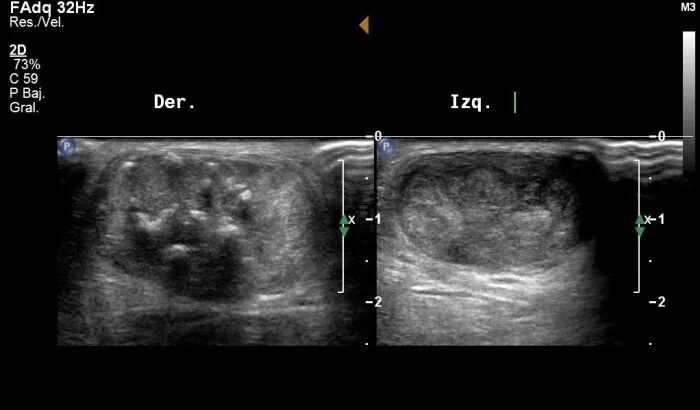

图:病理性 vs 正常跟腱超声比较

上面对比了症状侧与正常侧的超声表现:正常跟腱显示清晰、平行的纤维回声。

病理性跟腱明显增厚且回声模式破坏,甚至在一定程度上表现出血流信号。

对比帮助理解慢性腱病不是简单“炎症”,而是结构退变与血流代偿性变化并存的复杂过程。

而肌骨超声在跟腱病评估中具有明确优势,被多个指南推荐用于腱病的初始与随访评估。